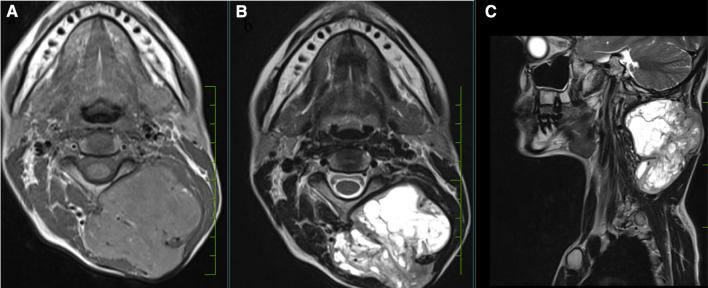

Fig. 2.

MRI neck: T1 hypointense (a) and T2 hyperintense (b, c) soft tissue lesion in left postero-lateral aspect of neck with no intramedullary extension

40-year-old lady presented in OPD with complains of swelling over nape of neck since last 7 years. Excision of swelling was tried 5 years ago but operating surgeon abandoned the procedure due to excessive bleeding. On examination there was 6 × 6 cm swelling over posterior aspect of neck extending from basi-occiput to 6th cervical vertebra with old excision scar over skin. On local ultrasound examination it was a well-defined, heterogenous lesion with multiple cystic spaces and vascular channels. X-ray neck (Lateral & AP view) (Fig. 1a, b) revealed a soft tissue density lesion in left postero-lateral aspect of neck with no bony erosion. MRI of neck revealed a T2 hyperintense and T1 hypointense lesion in subcutaneous plane with maintained fat planes with neck muscles and no intramedullary extension (Fig. 2a–c). As there was prior history of profuse bleeding during excision, we decided not to do the biopsy and instead decided to go for pre-operative embolization of tumour. But as there were multiple feeding vessels (Fig. 3), embolization of feeding vessels was cancelled after discussion with interventional radiologist.

On MRI, SFTs show low-intermediate intense T1-weighted images and heterogeneously low intense T2-weighted images in cases of hypocellular variants. Hypercellular variants appear hyperintense on T2-weighted images as are cystic degenerations, necrosis and hemorrhage [15].